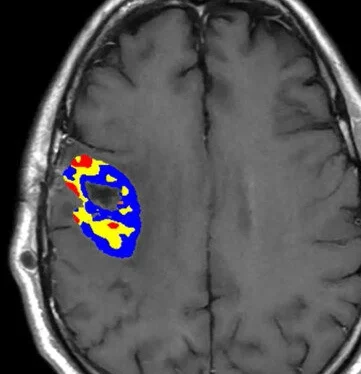

When it comes to brain tumor imaging, analysis software applications are NOT all created equal. Colorized functional maps may appear similar at first glance, but a closer look reveals critical differences in how they are calculated and their underlying meaning. Backed by over 30 years of focused research in Neuro-Oncology, Imaging Biometrics’s applications are trusted by leading brain tumor centers to provide imaging insights that help guide their most important decisions. IB sets the standard with a complete suite of applications for analyzing advanced MR images.

IB sets the standard with a complete suite of applications for analyzing advanced MR images. IB’s applications enhance standard anatomical imaging with key physiological information like true regions of contrast enhancement (void of post-surgical blood products), and tumor blood volume and flow, helping radiologists, surgeons and oncologists make better decisions for their patients. For patients who cannot undergo MRI, IB’s applications are also compatible with CT images. IB’s applications have been proven reliable and accurate in recent ground-breaking multi-center studies1,2 and are the most trusted by clinical trials researchers for their imaging needs3,4.